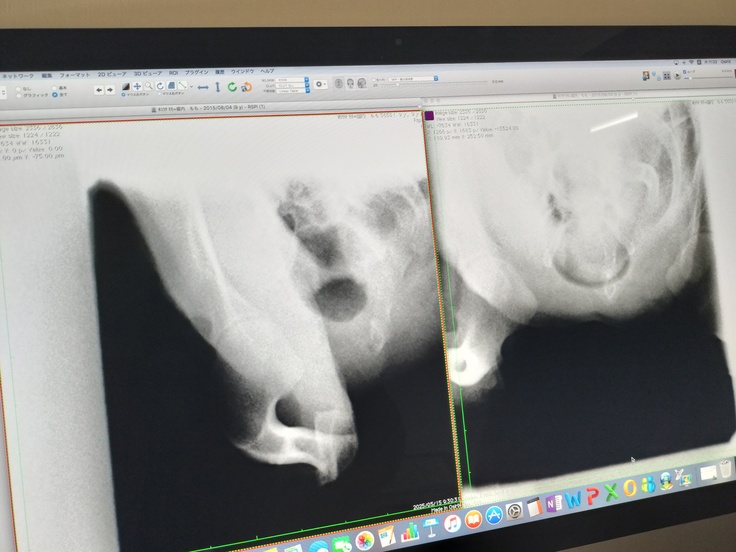

15日昼に退院。先生からの詳しい説明を頂きました。やはりかなり気管は潰れていてステージⅣだったそうです。

レントゲン写真でも潰れていた気管が丸くなったのがよくわかります。感動しました。

↑左が術後、右が術前です。綺麗な丸になっています。

カメラ画像です↓

↑左が術前右が術後です。

↑一番ひどい部分はほとんど 潰れており よく これだけの咳で収まっていたな と言われました。